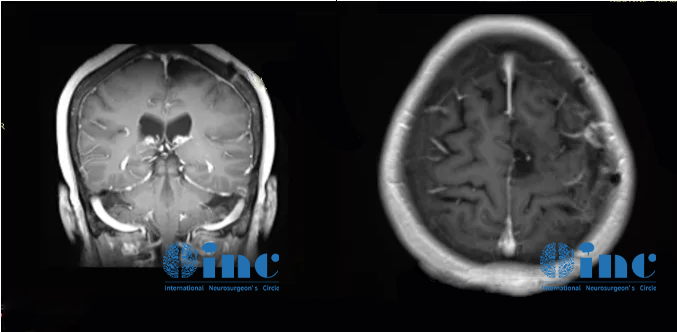

家人辗转求医最终找到INC德国巴特朗菲教授,王女士的治疗才迎来转机。在教授所在的德国INI国际神经学研究所、由INC德国巴特朗菲教授主刀的一场高质量手术直接全部切除了患者大脑深部复杂部位的脑膜瘤,她大脑中的“定时炸弹”被彻底摘除。如今手术已过去了1年半,从其术前MR、刚手术后的MR、术后1年半多的MR可以清楚看到未见复发迹象,患者现在一切生活如常,幸福的晚年生活不必再被可怕的肿瘤打扰。

术前MR

术后一年半MR